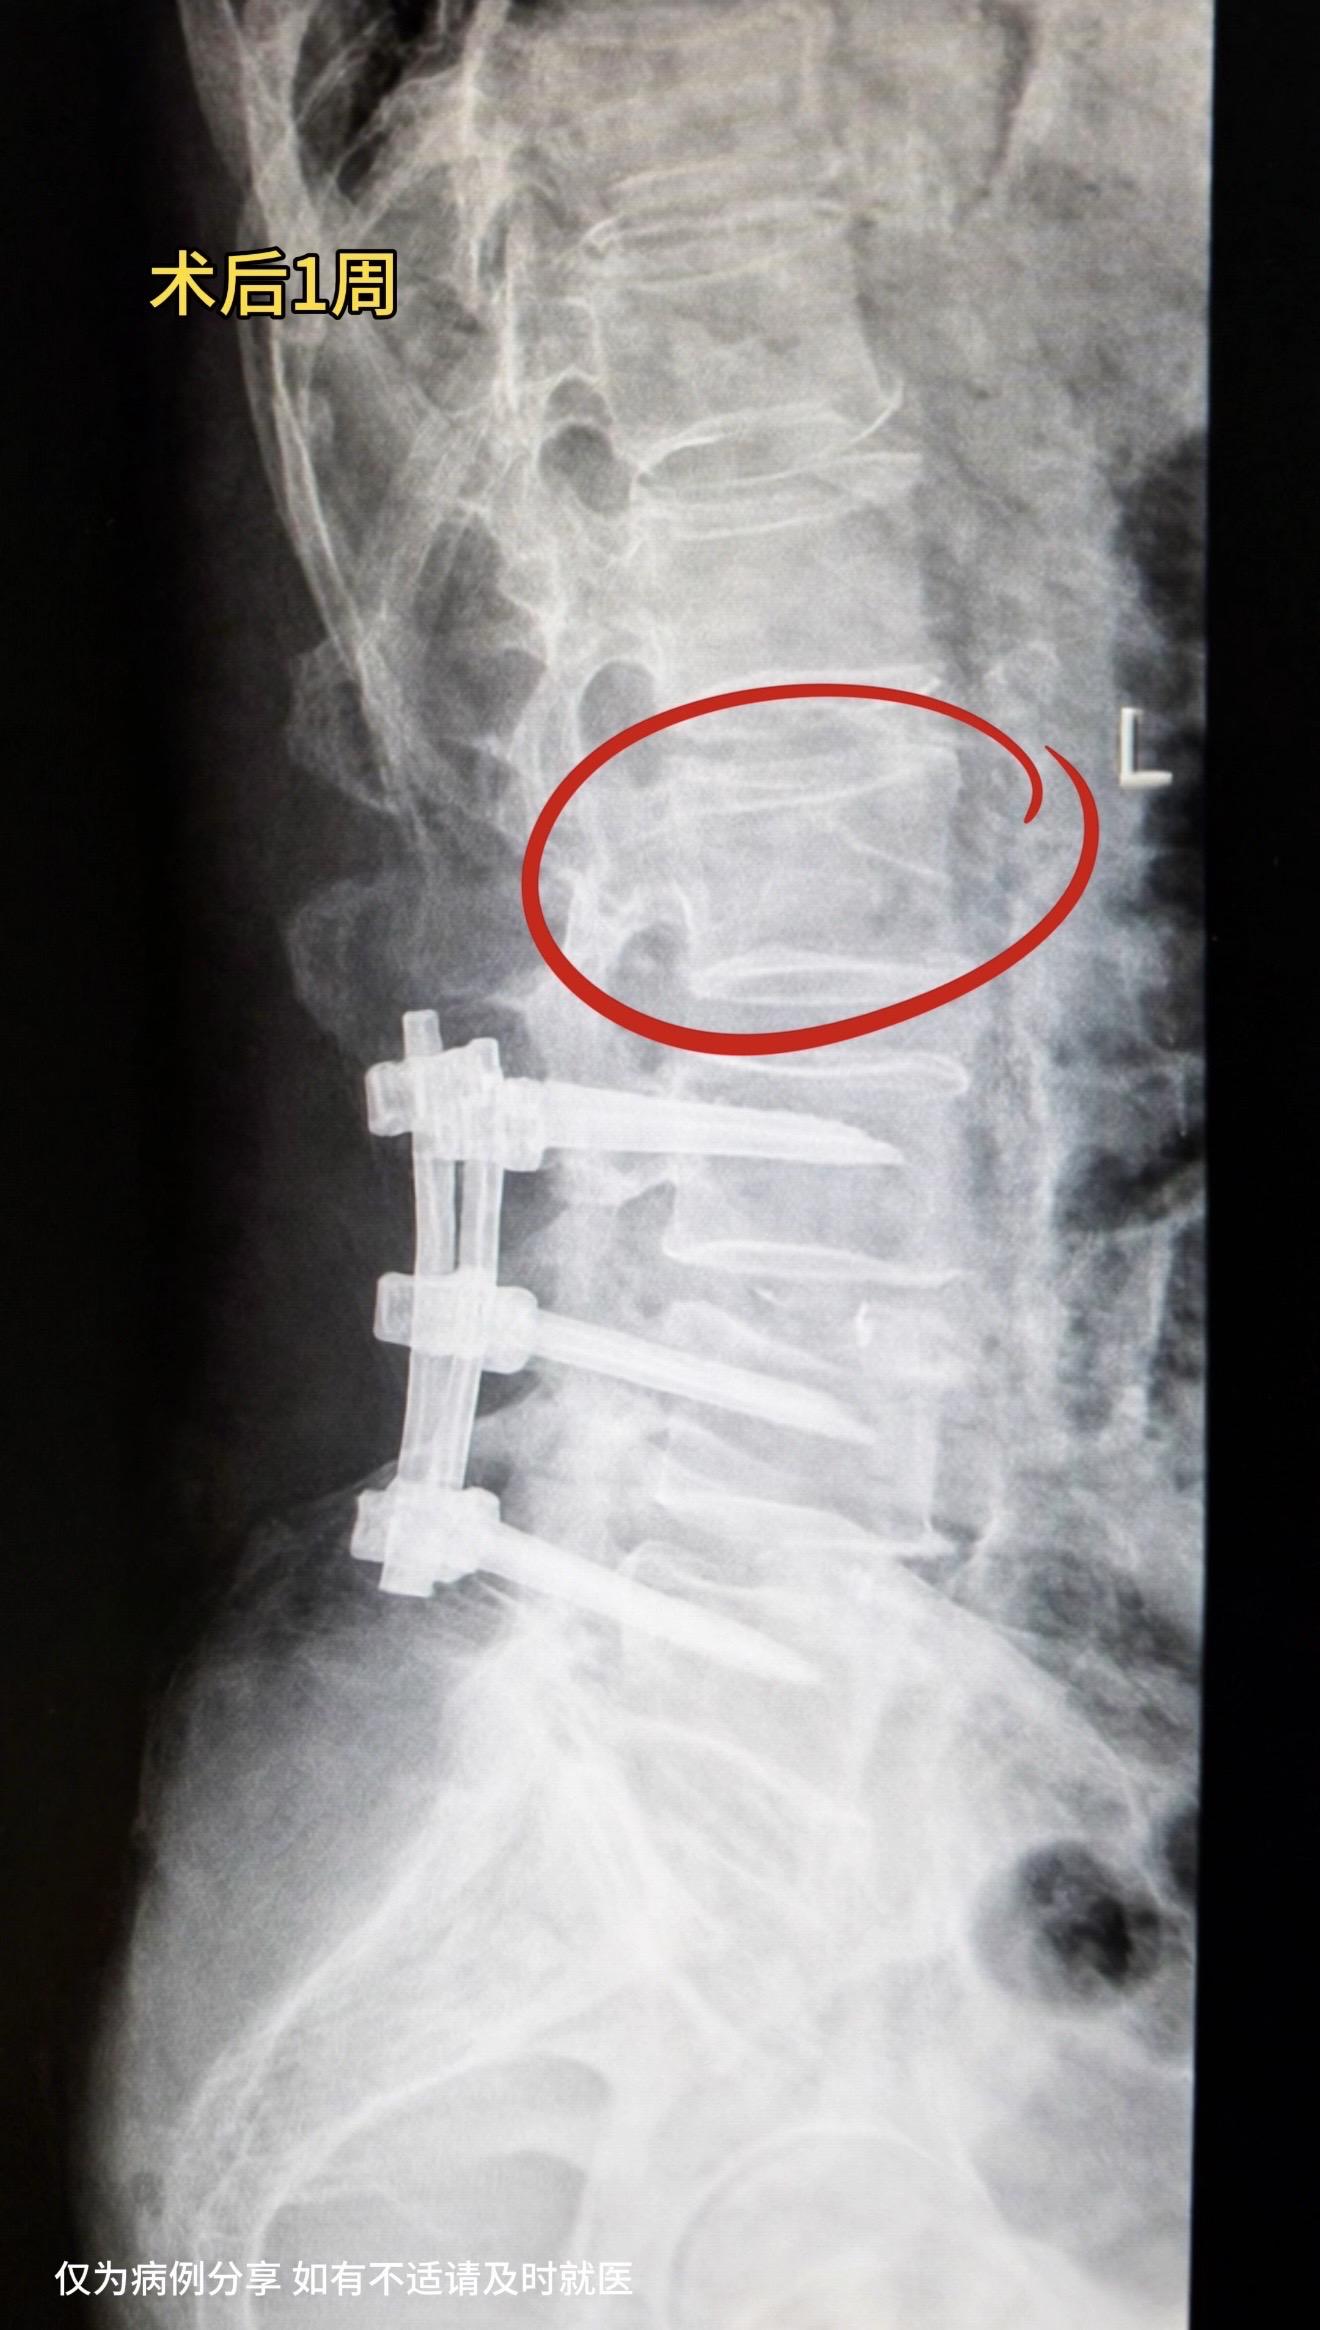

老年腰椎管狭窄症。老年腰椎管狭窄患者越来越多,很多伴有腰椎不稳定需要内固定,但坚强的内固定也带来很多问题,这是摆在患者和医生面前共同的难题。我们该如何选择? 真实病例分享: 70多岁男性,因严重腰椎管狭窄症半年前行腰椎内固定手术。术后恢复好,3月前去卫生间时扭了一下腰后,左下腹疼痛,现缓解。复查片子发现腰2压缩骨折,推测左下腹疼痛可能和腰2骨折神经刺激有关。 再骨折原因:1.坚强内固定上下应力集中;2.老年人骨质疏松,更加重了这种概率。